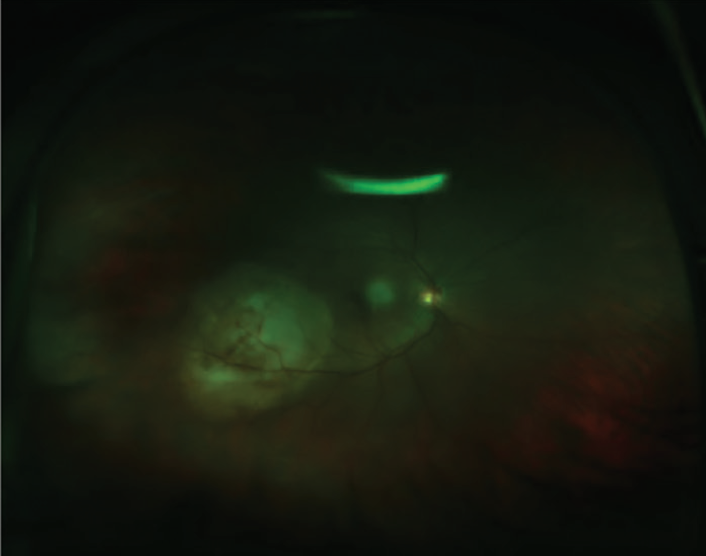

Figure 1. Color fundus photograph of the lesion highlights its orange color and location infratemporal to the macula.

When the patient presented for his ocular oncology appointment, he had not developed any discomfort or pain in his eyes since his appointment with a referring physician that week. His VA was 20/100-1 OD and 20/60+2 in his left eye (OS). Posterior segment evaluation OD was significant for an elevated mass temporal to the macula, 4.5 by 8.0 disc diameters in size. Fundus photography of the lesion highlighted its orange color and size (Figure 1). Fluorescein angiography showed the mass infratemporal to the macula (Figure 2). Ocular ultrasound revealed an elevated posterior pole mass, 12 mm by 14 mm in size, with high internal reflectivity (Figure 3). Ultrasound A-scan demonstrated an area of increased reflectivity (Figure 4). The presumed diagnosis was choroidal metastasis from the patient’s active thyroid cancer.

The patient had a single focus of metastasis, which is common; however, multiple foci of metastasis are not uncommon, as seen with other manifestations of metastatic cancer.8 These metastatic foci are typically described as yellow or creamy flat patches, as compared with the typical brown color associated with melanoma. Interestingly, orange-colored metastatic lesions similar to that shown in our patient in Figure 1 are due to lipofuscin-laden macrophages released from damaged retinal pigment epithelial cells.1,3,4 These lesions likely represent spread from tumors such as thyroid, renal, and carcinoid cancers.1 Lesions from the more common breast and lung tumors are typically brown.